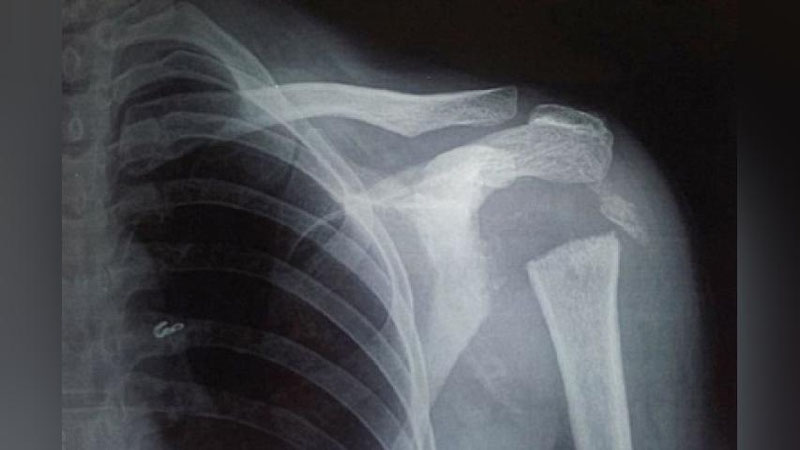

Ayolning elkasini tekshirib ko`rgan mutaxassislarni uning judayam yumshoqligi, bemor qo`lini orqaga bemalol aylantirishi o`ylantirib qo`ydi. Rentgen natijalari esa elka va kurakni birlashtiruvchi suyakning yo`qolib qolganligini ko`rsatdi. Magnit-rezonans tomografiyasi ham bu holatni tasdiqladi.